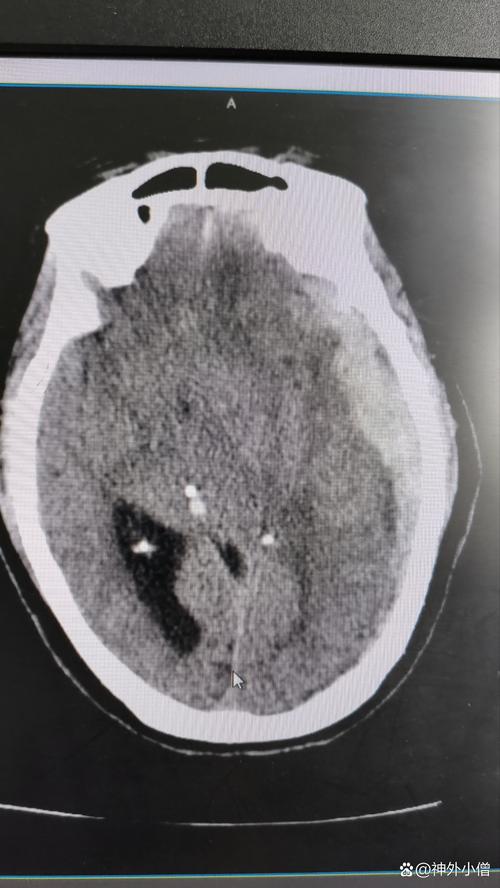

颅脑损伤 → 脑疝 → 脑梗

这是一个病情急剧恶化的典型过程,下面我们逐一分解。

- 颅内血肿: 如硬膜外血肿、硬膜下血肿、脑内血肿,血液不断积聚,会占据颅腔空间。

核心问题: 无论是血肿还是水肿,都会导致一个致命的问题——颅内压增高。

脑疝

是什么? 脑疝是颅脑损伤(或其他导致颅内压增高的疾病,如肿瘤、中风)最危险的并发症,是危及生命的信号。